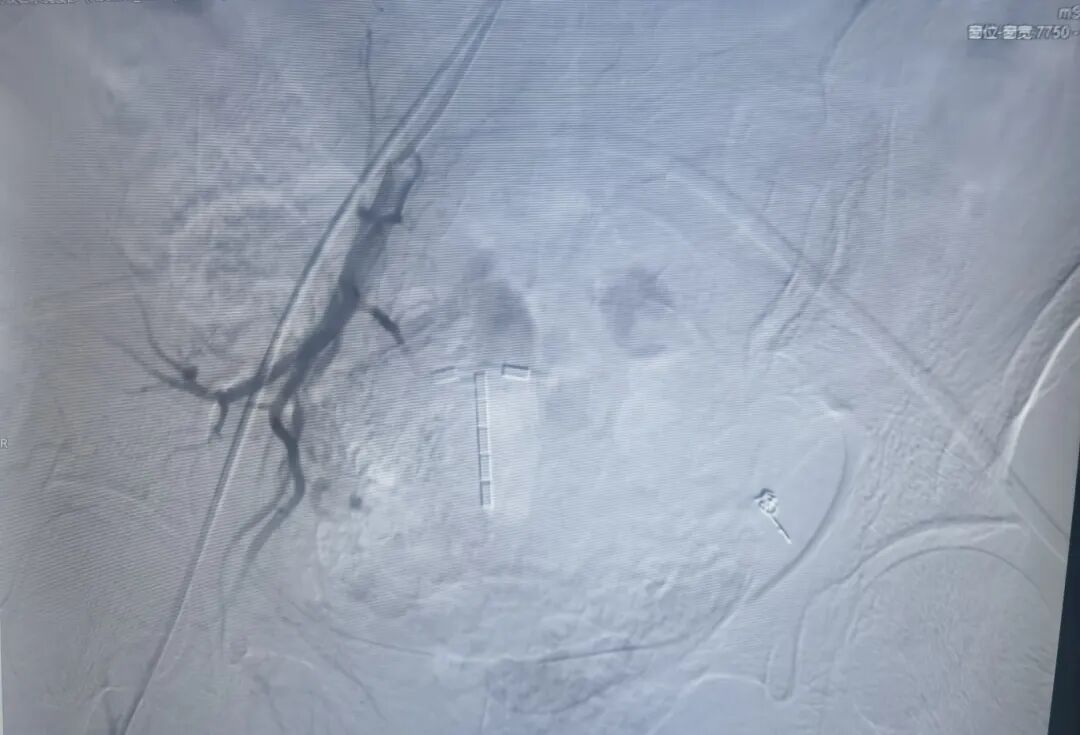

右侧子宫动脉栓塞术后

与传统介入科室多专注于放射介入不同,赣州市妇幼保健院介入科自成立以来,始终坚持技术创新与全面发展,科室已建立起完善的双介入技术体系。其中超声介入凭借其实时、精准、无辐射的优势,在各部位穿刺活检、置管引流、囊肿治疗、消融治疗等方面发挥着重要作用。放射介入依托先进的数字减影血管造影(DSA)设备,在血管栓塞、肿瘤介入、出血急救等领域展现独特价值。此次开展的DSA引导下子宫动脉栓塞术,正是放射介入技术在高危出血救治中的经典应用,标志着介入科已具备开展高难度介入手术的全面能力。